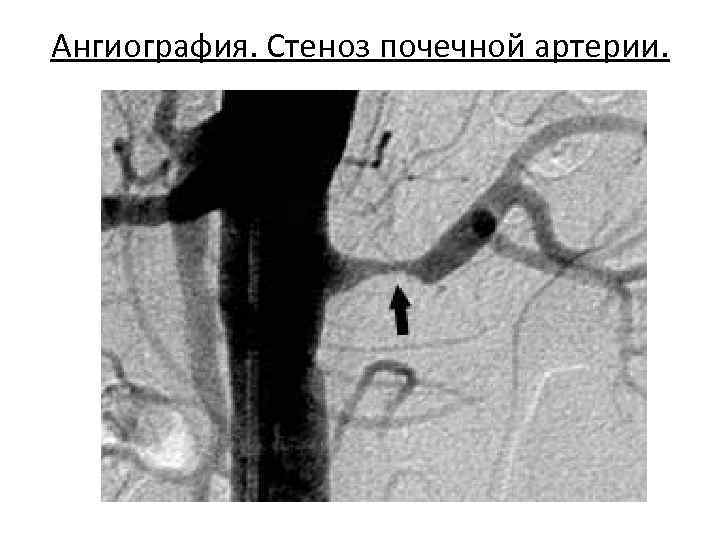

Рентгенодиагностика • Применяют экскреторную урографию, которая позволяет оценить функциональное состояние почек и выявить ишемию. • Наиболее достоверным методом диагностики служит селективная ангиография почечных артерий, позволяющая судить о природе процесса, степени стеноза и локализации патологического процесса.

Ангиография. Стеноз почечной артерии.